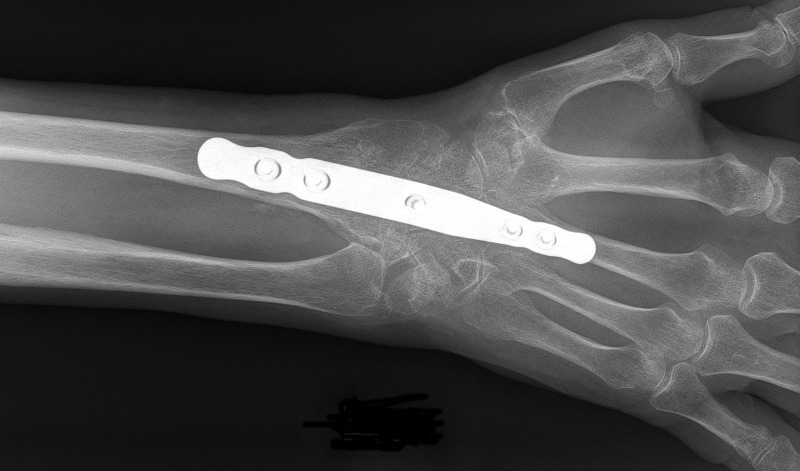

손목 골절치료는 부상 정도와 골절의 형태에 따라 치료방법이 다른데요.

단순 골절은 수술 없이 뼈를 맞춘 후 깁스로 고정 치료가 일반 적입니다.

하지만 복합골절이나 사선으로 뼈가 부러지는 경우에는 수술을 시행하고 깁스를 한 뒤 약 2달가량 고정하고 있어야 합니다.